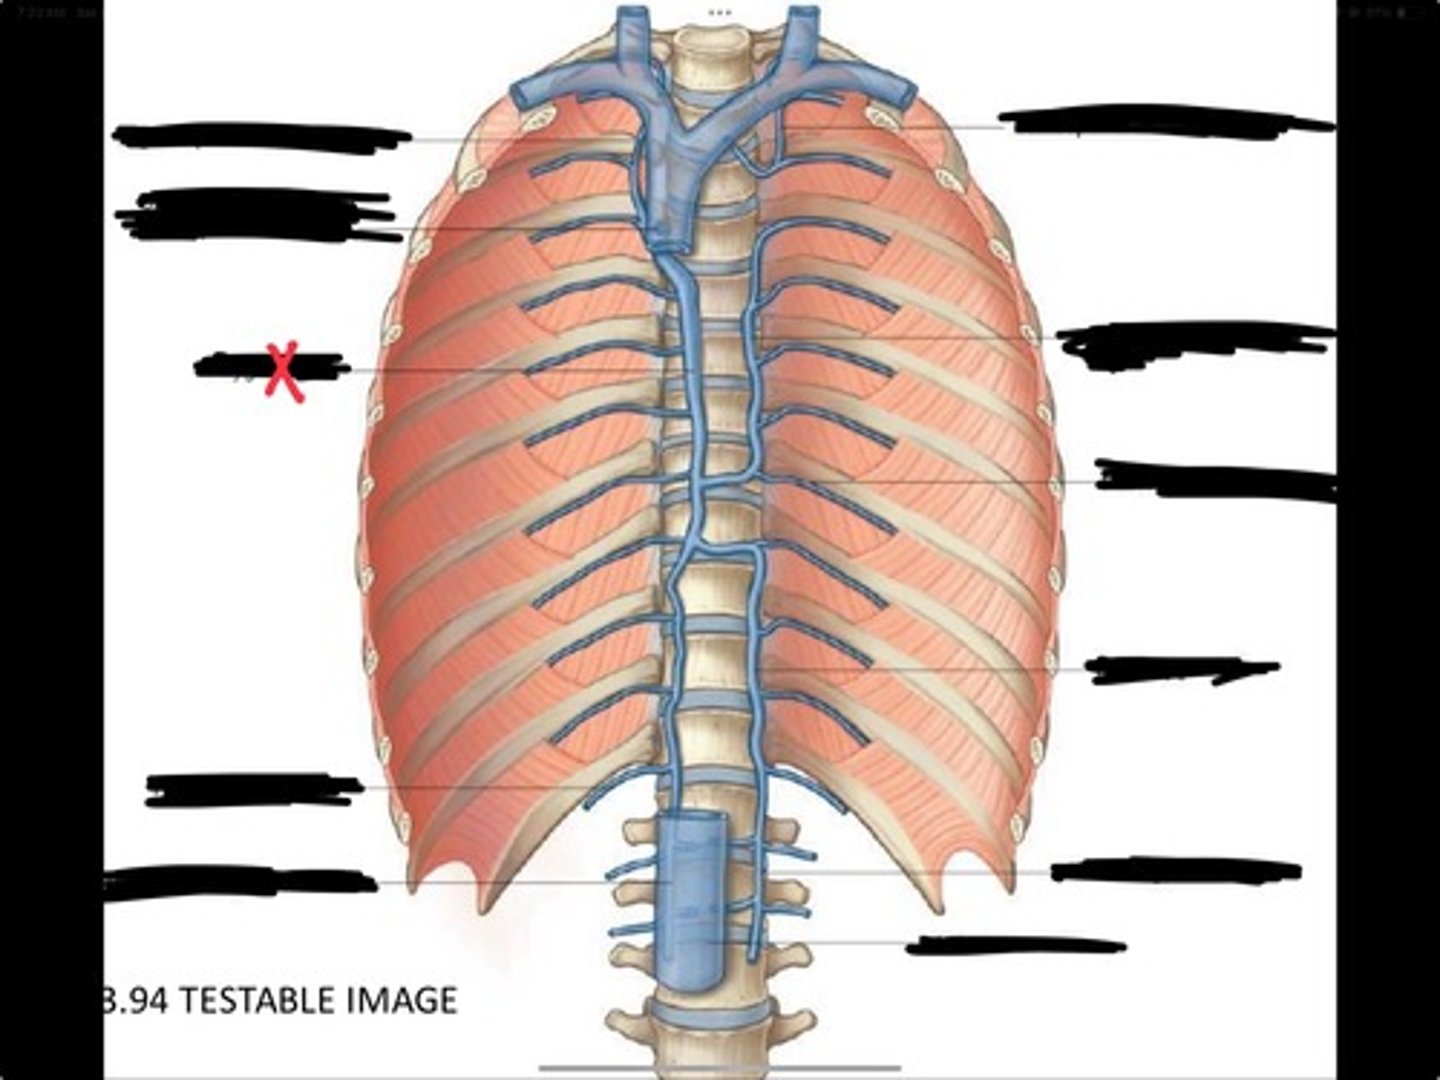

Right ascending lumbar vein

Right subcostal vein

Azygos vein

Opening of the azygos vein into superior vena cava

Right superior intercostal vein

Left superior intercostal vein

Accessory hemiazygos vein

Posterior intercostal vein

Hemiazygous vein

Ascending lumbar vein